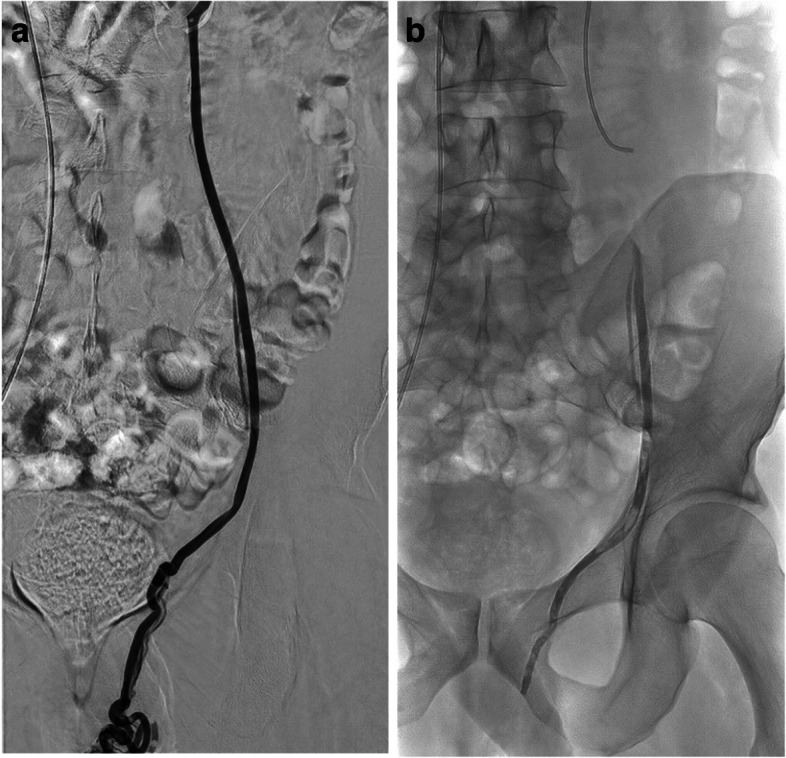

Purpose: Our purpose was to assess the feasibility and the short-term safety and efficacy outcomes of a wide range of transcatheter arterial and venous embolisation procedures done using α-hexyl-cyanoacrylate (AHCA)-MagicGlue® in patients with bleeding and non-bleeding disorders.

Methods: This single-centre retrospective study included consecutive patients who underwent emergent or planned AHCA-MagicGlue® transcatheter embolisation between February 2019 and September 2023. Technical success, clinical success, 30-day mortality, and complication rates were evaluated.

Results: We included 101 patients with a mean age of 49.9 ± 20.5 years who underwent arterial (n = 43, 42.6%) or venous (n = 58, 57.4%) embolisation for bleeding (n = 16, 15.8%) or other reasons (n = 85, 84.2%). The technical success rate was 100%. After a mean follow-up of 2.2 months, the clinical success rate was 94% in patients with bleeding and 95% in other patients; 1 patient died of multi-organ failure unrelated to the procedure. In the 22 patients with prostatic artery embolisation, statistically significant improvements were recorded at 3 months versus baseline for the International Prostate Symptoms Score (IPSS) (10.0 ± 5.8 vs. 20.8 ± 7.3, p = 0.001), IPSS quality-of-life score (2.0 ± 1.4 vs. 5.0 ± 1.0; p = 0.001), and prostate volume (67.8 ± 38.0 mL vs. 96.7 ± 47.4 mL, p = 0.001). Adverse events occurred in 11 (10.9%) patients and were major in 4 and minor in 7 patients.

Conclusions: MagicGlue® transcatheter arterial and venous embolisation is feasible, effective, and safe for bleeding and non-bleeding conditions across a broad range of anatomic sites.